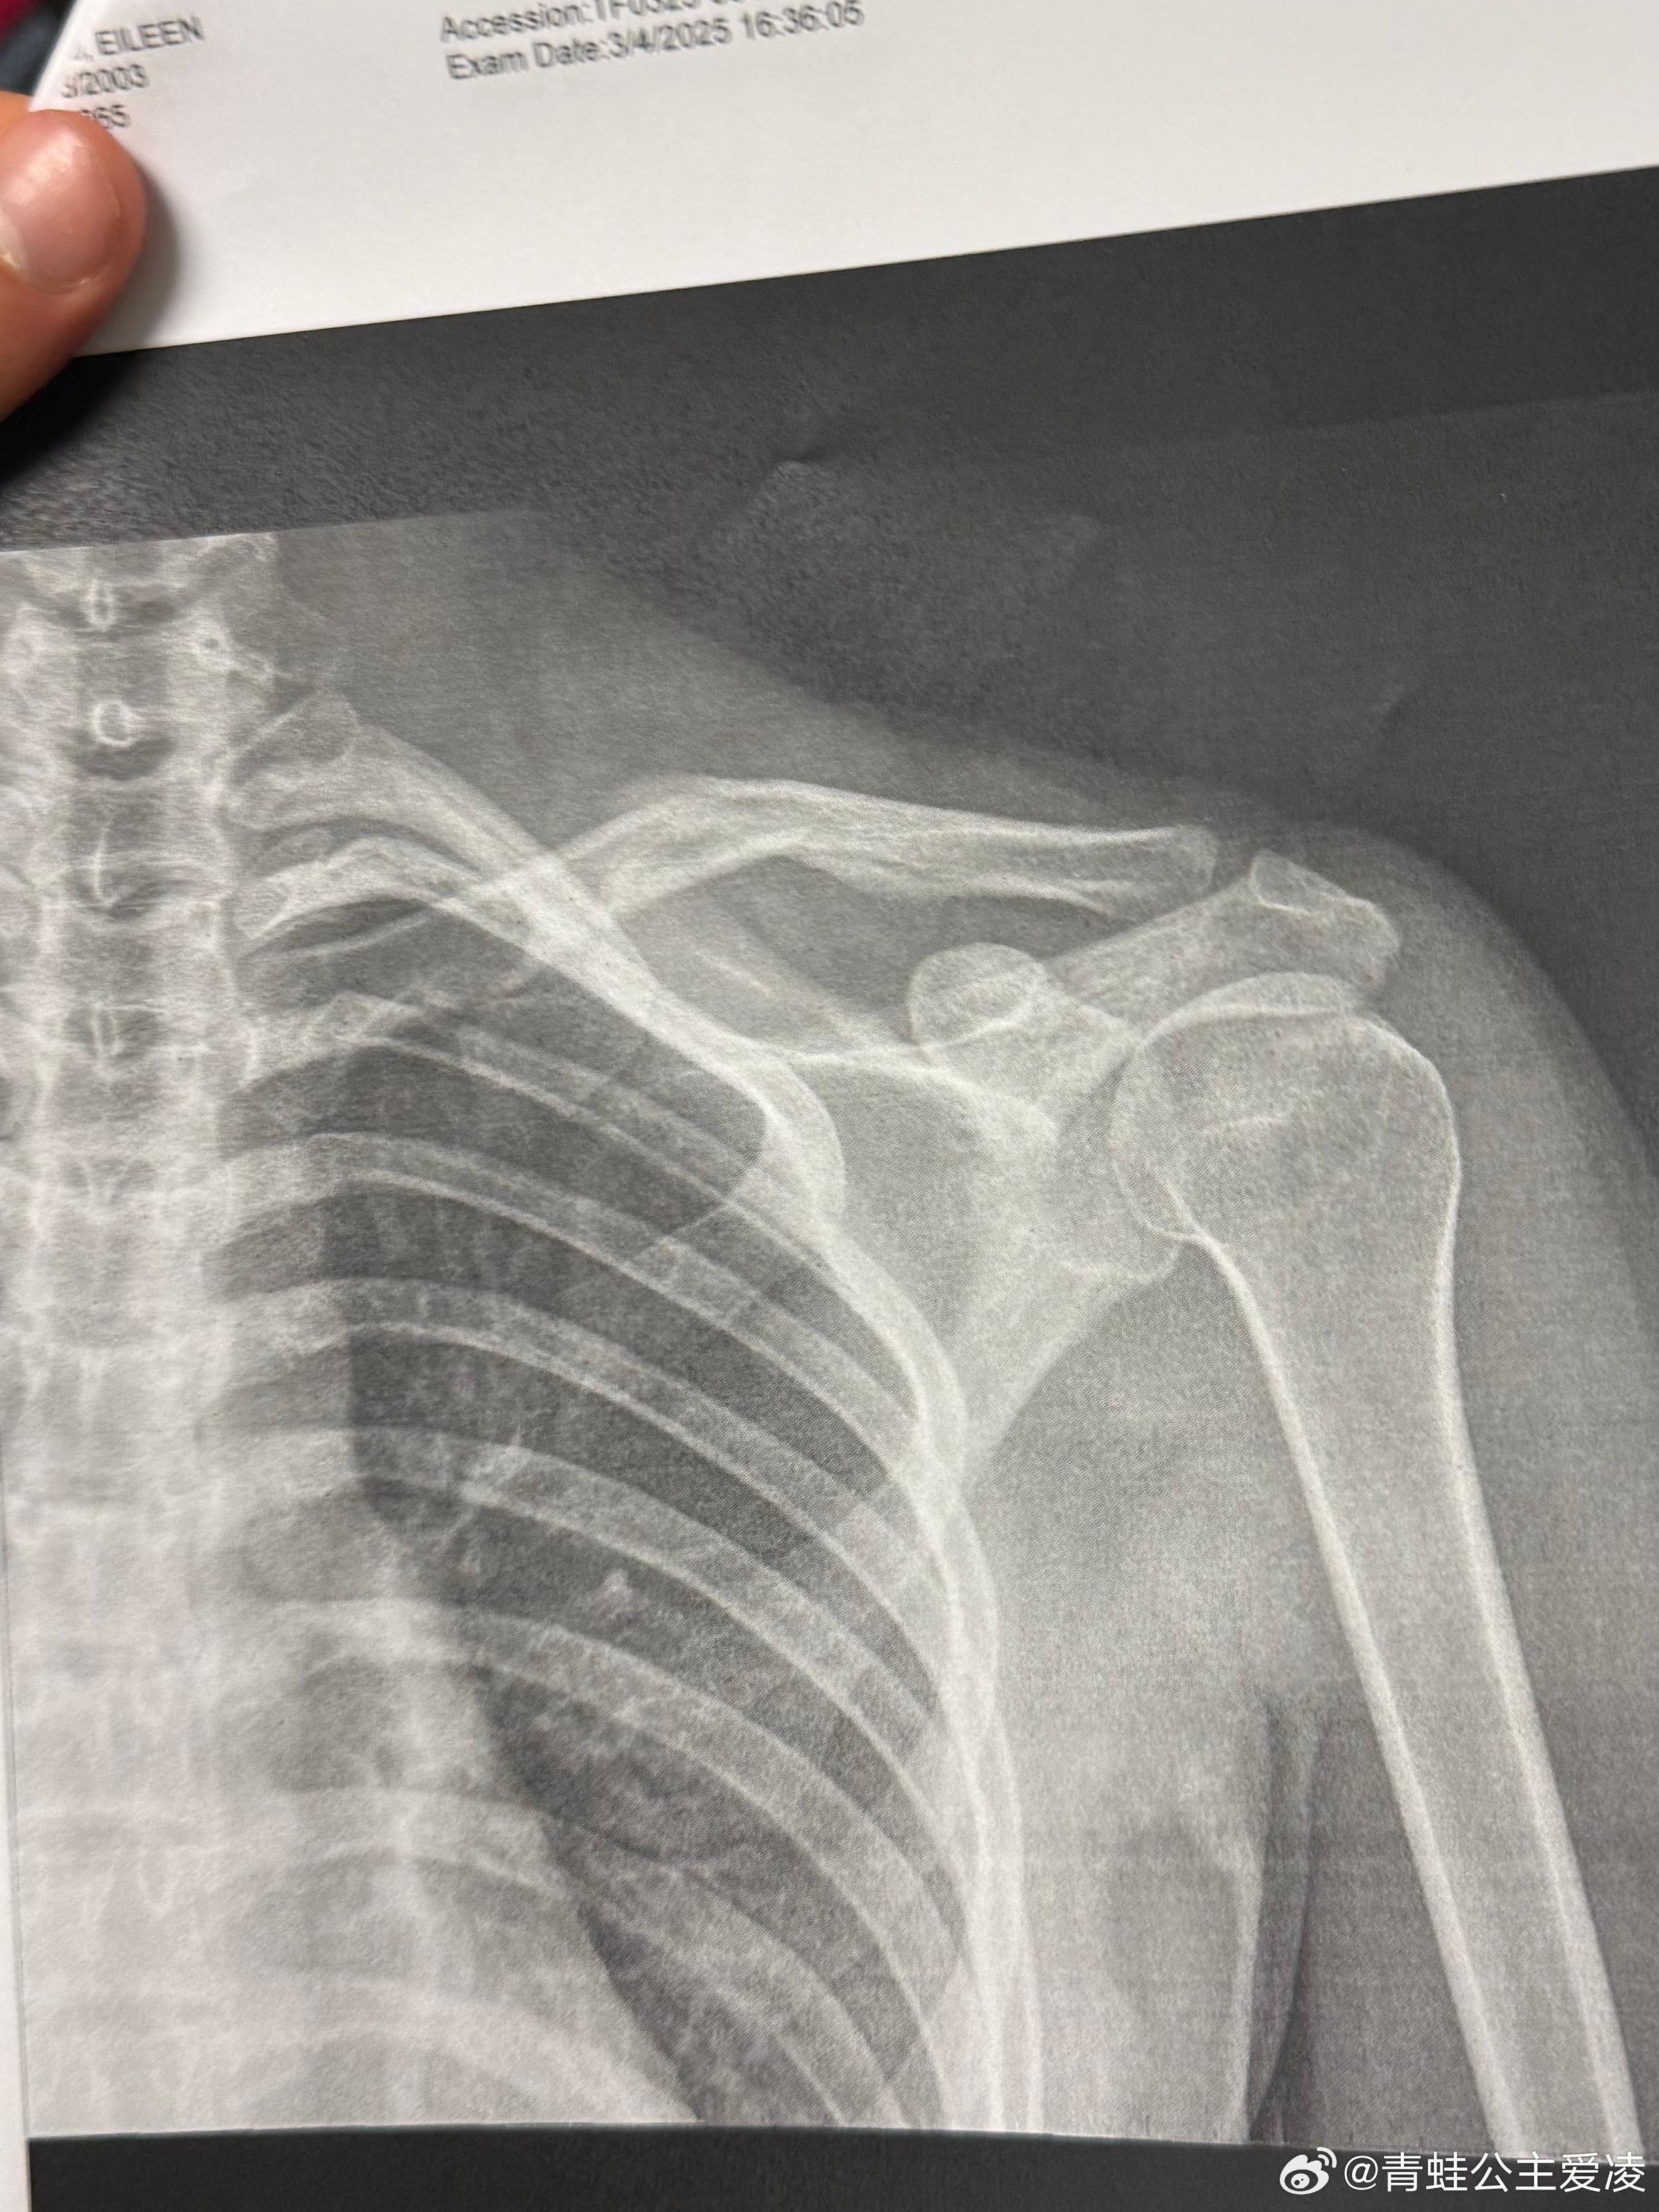

谷愛凌曬肩部骨折X光照!憾受傷無緣亞冬會惹網民心痛

北京冬奧滑雪兩金得主谷愛凌(Eileen Gu)日前在微博曬出骨折的X光照,令內地網友心疼不已。據悉,上月4日,谷愛凌曾宣布因傷退出在哈爾濱舉行的亞冬會。

3月9日,谷愛凌在社交平台上載了肩部骨折的X光照片,並配上「心碎」的表情。這消息迅速衝上微博熱搜,令網友十分心痛,紛紛送上祝福:「注意身體,早日康復,期待你重回賽場! 」還有人引述巴黎奧運金牌得主全紅嬋的經驗,認為谷愛凌可能和全紅嬋一樣,「隨著年齡增長,身體各部分重量變化了,整體協調性要有個適應過程, 這段時間內做動作可能就各種轉不過來」。

據先前傳媒報道,谷愛凌上月4日曾在微博發文稱,「我在Aspen Xgames(冬季極限運動)比賽受傷後,為了能參加緊接其後的世界盃比賽,在訓練中不幸再次受傷。今天我不得不懷着沉重的心情退出盼望已久的哈爾濱亞冬會。」